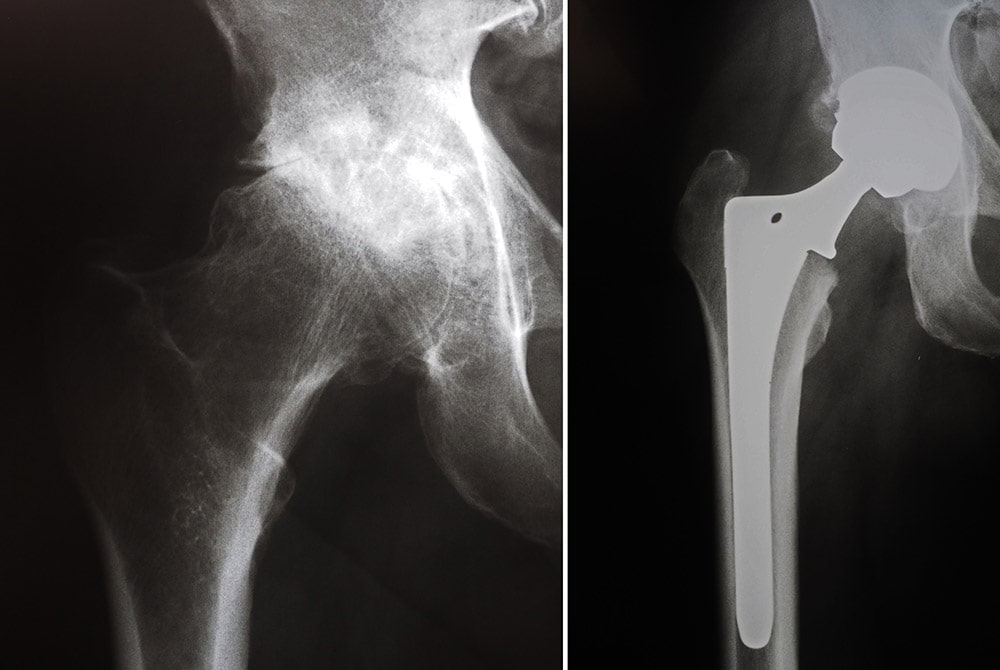

The prosthesis mimics the shape and movement of a natural joint. For example, in an arthritic hip:

• The damaged ball (the upper end of the femur) is replaced with a metal or ceramic ball attached to a metal stem that is fitted into the femur.

• A plastic liner is inserted into a metal socket, which is implanted into the pelvis, replacing the damaged socket.

ip with osteoarthritis and hip with hip implant

(Left) A hip with osteoarthritis. (Right) The head of the femur and the socket have been replaced with an artificial device.

arthritic hip and hip replacement

X-rays show an arthritic hip before and after total hip replacement.